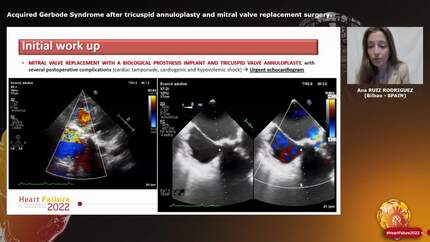

Miss A. Ruiz Rodriguez (Bilbao, ES)